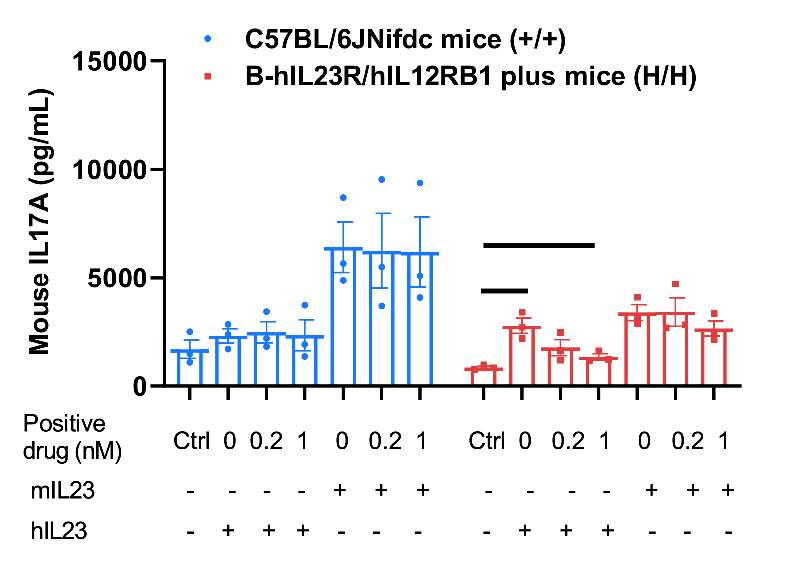

Function analysis of IL23R in wild-type C57BL/6JNifdc mice and homozygous B-hIL23R/hIL12RB1 plus mice by ELISA. Splenocytes were collected from wild-type C57BL/6JNifdc (+/+) mice and homozygous B-hIL23R/hIL12RB1 plus mice (H/H), then CD4+ T cells were isolated and cultured on anti-mCD3ε antibody and anti-mCD28 antibody pre-coated plates, and stimulated with indicated concentrations of mouse IL23 recombinant protein (10 ng/mL) or human IL23 recombinant protein (10 ng/mL), and different concentrations of positive drug (0 nM, 0.2 nM, 1 nM) at 37℃ for 48 h. Cell supernatants were collected for ELISA analysis of mouse IL17A (BioLegend, 432504). Mouse IL23 can induced mouse IL17A production in wild-type C57BL/6JNifdc mice and homozygous B-hIL23R/hIL12RB1 plus mice. Human IL23 can induced mouse IL17A production in wild-type C57BL/6JNifdc mice and homozygous B-hIL23R/hIL12RB1 plus mice. The positive drug can inhibit the expression of mouse IL17A in homozygous B-hIL23R/hIL12RB1 plus mice with hIL23 stimulated. The positive drug is provided by the client.